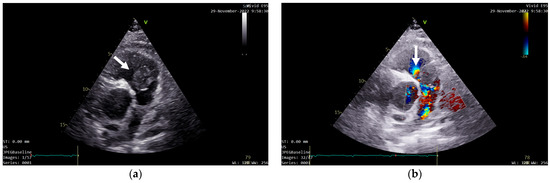

A transthoracic echocardiography (TTE) was performed. It showed a round 25/30 mm, 6.5 cm2 intracardiac mass attached to the right ventricle outflow tract (RVOT) wall by a 5 mm thick pedunculus (Figure 1a), which prolabated through the pulmonary valve in systole, thus causing severe obstruction at this level with a maximum gradient of 70 mmHg (Figure 1b and Figure 2). The pulmonary valve itself presented no structural abnormalities, but the right ventricle was dilated (50 mm at the base) with a slightly decreased systolic function (TAPSE = 15 mm), a moderate tricuspid regurgitation and paradoxical interventricular septum motion being also observed due to right ventricular pressure overload. The left ventricle was not dilated and had a preserved systolic function, and only a mild mitral regurgitation was noted.

Figure 2. TTE Continuous Wave Doppler showing severe RVOT obstruction.